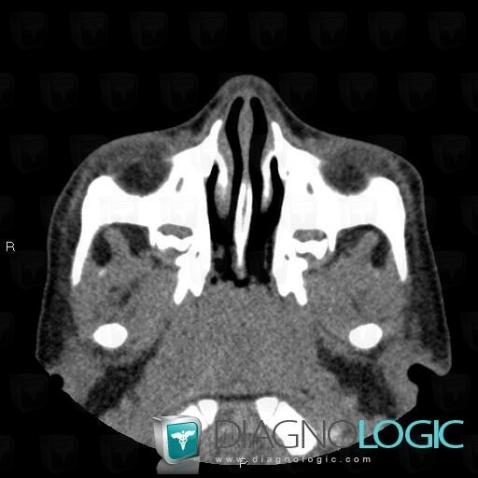

- Diagnosis Adenoid hypertrophy, Location(s) Nasal cavity / Nasopharynx, with gamuts Nasopharyngeal lesion